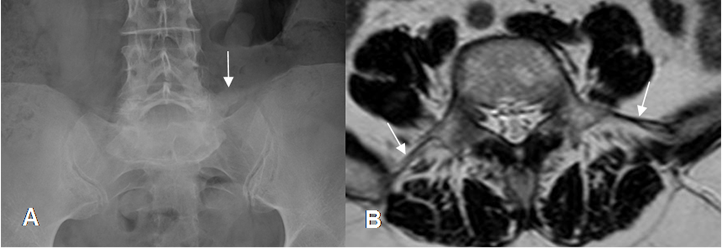

Fig 30 B. Lumbarización de S1.

A: Rx AP y B: Rx lateral. Presencia de 6 segmentos lumbares. 12º costilla (Flecha delgada).

C: RM sagital en T2. Arteria renal izquierda entre L1-L2, como punto de referencia y se confirman los 6 segmentos lumbares.

Fig 31. Ligamento iliolumbar.

A: Rx AP. Calcificación del ligamento iliolumbar izquierdo.

B: RM axial en T2. Ligamento iliolumbar normal.